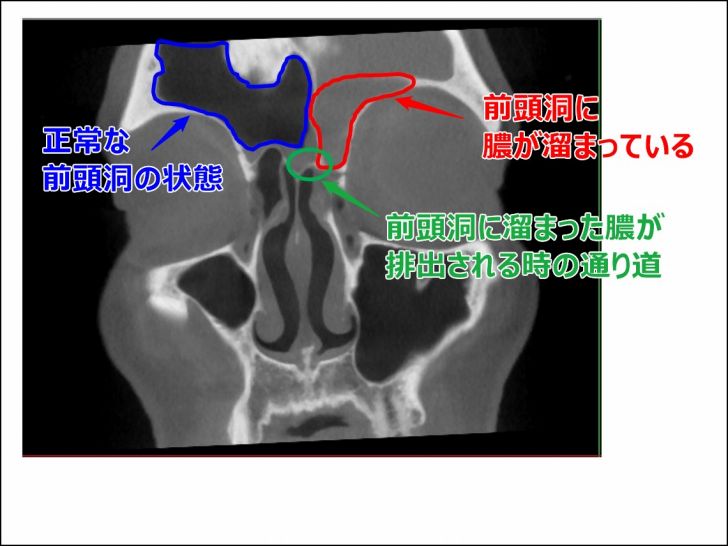

2016年11月の副鼻腔

術後の経過を順調に過ごしていたものの、手術から1年半が経って急に頭痛が再発しました。

その時にもCTを撮影しましたが、その画像はもらえなかったので2015年8月のCTを違う角度から見た時の画像です。

▼それがこちら

1度目の術後は2つの病院で診てもらいましたが、その手術は「完璧と言えるほどに綺麗な手術がされている」と両方の病院で言われました。

問題は左目の上(おでこあたり)の前頭洞の膿です。

[su_note note_color=”#ffffcc” radius=”0″]

【画像解説】

上記画像の通り、左前頭洞にはまた膿が溜まっていました。

これによって左前頭洞周辺が炎症を起こし、神経を圧迫して頭痛が起こっているとのこと。

また右側の前頭洞は全くもって膿は溜まっておらず、正常な状態でしたが、悪くはないけど異常発達があるとのこと。

そして緑色のところが、前頭洞と鼻の穴をつないでいる通り道でしたが、ここにも一般の人と比べると違いがあると言われました。

[/su_note]

➀前頭洞の空洞の発達が一般的な人の2倍!

前頭洞とはおでこ周辺のあたりのことを差し、大体は目じり辺りまでが空洞になっている程度が一般的だそうです。

僕の場合、前頭洞としての空洞がこめかみの後ろ辺りの方まで発達しているとのことでした。(悪いことはなくてむしろ良いらしい…ホントかは分かりませんが)

➁右前頭洞が左にはみ出ている

前頭洞は左右にありますが、左右対称ということはほとんどないみたいです。

上記画像を見てもらっても分かりますが、青枠で囲ったところが真ん中より少し右の方に出ています。(画像左側が顔の右部分になります)

このおかげで左前頭洞が押しやられて、少し狭くなる現象が起こります。

③左前頭洞の膿を排出するはずの通り道が一般的な人の2分の1!

右前頭洞が左にのびているおかげで、左前頭洞の空洞が狭くなっているとの事でした。

そもそもこの通り道は他の副鼻腔と比べると狭い通り道なんだそうですが、このせいで僕の左前頭洞の膿を排出するべき通り道の広さは、一般的な人の2分の1しかないんだとか。

これが頻繁に左前頭洞に膿が溜まって炎症を起こす原因だったんです。